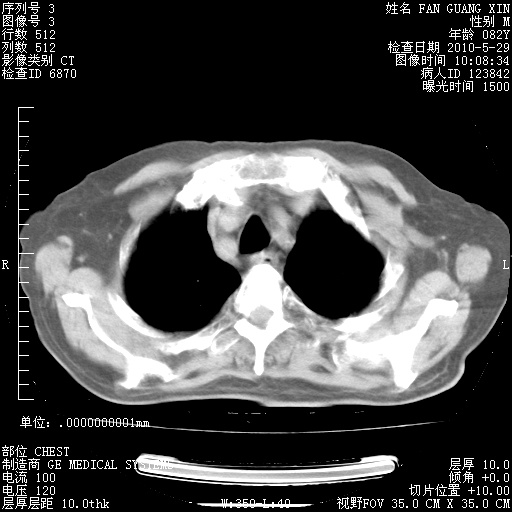

治疗3周后的肺部CT纵隔窗

再治疗10天后的肺部CT 纵膈窗

阅读此次胸部CT,肺间质渗出性改变较入院时有吸收。目前从体温、白细胞、中性分叶明显增高,肯定存在细菌感染(发生医院感染哦,若无消化道及泌尿系统等感染的依据,肺部感染可能大)。若你院头孢哌酮舒巴坦钠耐药率较高,同意你的方案,若48小时体温仍高,可考虑使用碳青霉稀类抗菌药物,同时可予超声雾化、注意滴数时加大液体量。白蛋白33.30g/L较低哦,需加强营养等支持治疗。